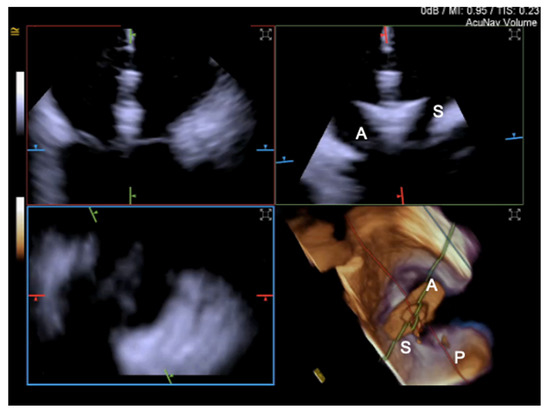

3.2. Intracardiac Echocardiography: Strenghts and Limitations

- Pozzoli, A.; Taramasso, M.; Zuber, M.; Maisano, F. Transcatheter tricuspid valve repair with the MitraClip system using intracardiac echocardiography: Proof of concept. Eurointervention 2017, 13, e1452–e1453. [Google Scholar] [CrossRef] [PubMed]

- Tang, G.H.; Yakubov, S.J.; Soto, C.E.S. 4-Dimensional Intracardiac Echocardiography in Transcatheter Tricuspid Valve Repair with the MitraClip System. JACC Cardiovasc. Imaging 2020, 13, 1591–1600. [Google Scholar] [CrossRef]

- Silvestry, F.E.; Kadakia, M.B.; Willhide, J.; Herrmann, H.C. Initial experience with a novel real-time three-dimensional intracardiac ultrasound system to guide percutaneous cardiac structural interventions: A phase 1 feasibility study of volume intracardiac echocardiography in the assessment of patients with structural heart disease undergoing percutaneous transcatheter therapy. J. Am. Soc. Echocardiogr. 2014, 27, 978–983. [Google Scholar] [CrossRef]